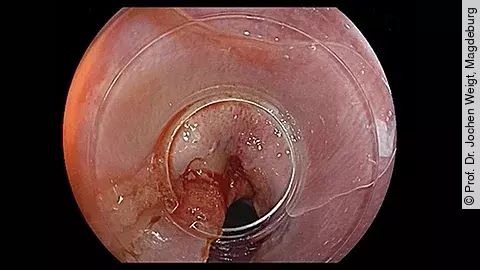

PEG-KomplikationVerschluss des Ostiums durch Clip-System

Im neuen Video präsentiert PD Dr. Jochen Weigt den seltenen Fall einer schweren lokalen Komplikation nach PEG-Anlage. Bei einer 61-jährigen Patientin wurde eine PEG gelegt. Sechs Tage später stellte sie sich mit Wundproblemen und Schmerzen vor.